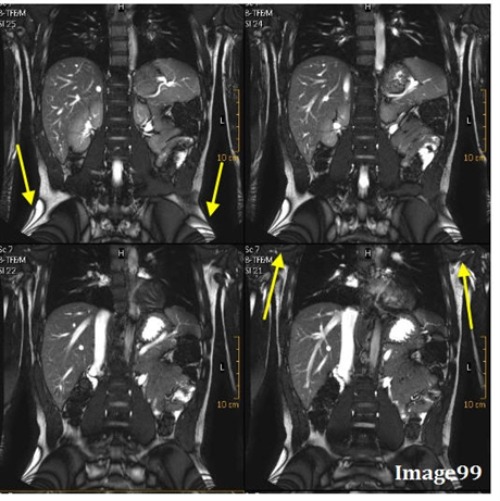

The artifact in Image 99 is caused by:

A. Interference of aliased signals at different phases

B. When a small matrix is used, it incompletely digitizes the echo by the end of the acquisition

C. Undersampling

D. Differing frequencies of fat and water

The arrows in Image 99 are pointing to a zebra-like artifact caused by interference patterns. What is this artifact called?

A. Gibbs truncation

B. Cross talk

C. Moire

D. Wraparound (aliasing)